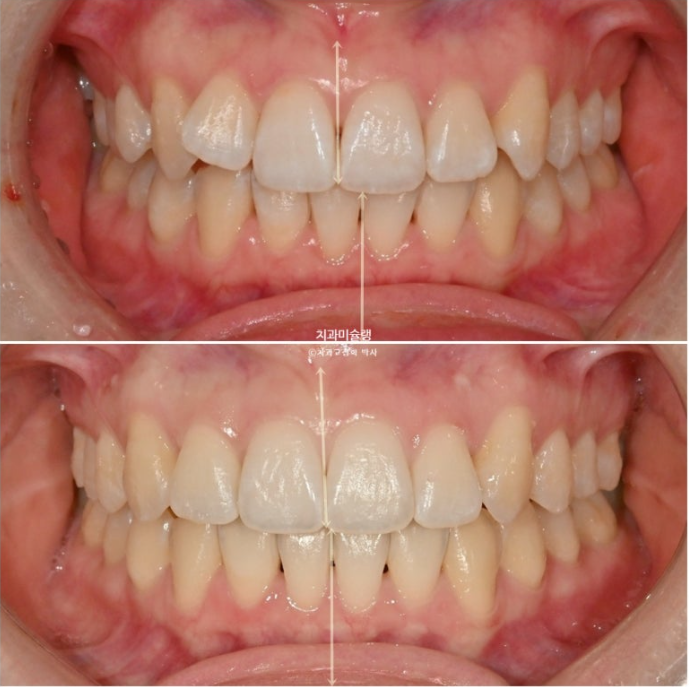

정면사진에서 블랙트라이앵글, 중심선 불일치 등이 보입니다.

덧니쪽으로 중심선은 치우치기 마련이지만 그 이외에도 양쪽 어금니 교합관계가 다르다 보니 중심선 불일치가 크게 나타납니다.

중심선 불일치가 미세하게 남았지만 만족스럽게 개선되었으며

윗니 정중앙 블랙트라이앵글은 치간삭제를 통해 줄였으며

중심선은 처음에 비해 많이 개선되었습니다.

앞니 높낮이는 완벽한 대칭을 이루고 아랫입술과 조화로운 호를 그립니다.

미소가 깔끔해졌습니다.